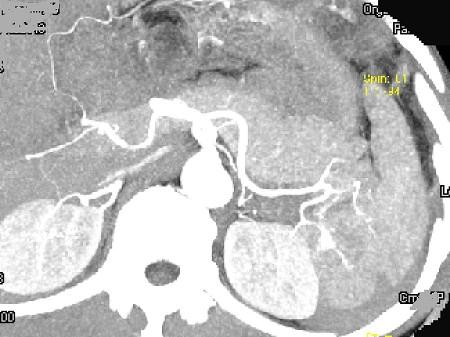

问题 男,55岁,左上中腹部突发性疼痛,CT扫描如图,最可能的诊断是 ( )

选项 A、脾脓肿 B、脾转移瘤 C、脾淋巴瘤 D、脾血管瘤 E、脾肿瘤破裂出血

答案 E